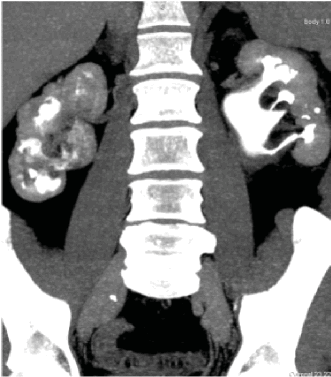

По данным спиральной компьютерной томографии, выявлены множественные конкременты обеих почек, а также кальцинированные лимфатические узлы брыжейки тонкой кишки (рис. 1).

Рисунок 1. КТ после нефростомий. Множественные камни почек и кальцинированные лимфоузлы брыжейки

Figure 1. CT-scan after nephrostomy. Multiple kidney stones and calcinated mesenteric lymph nodes